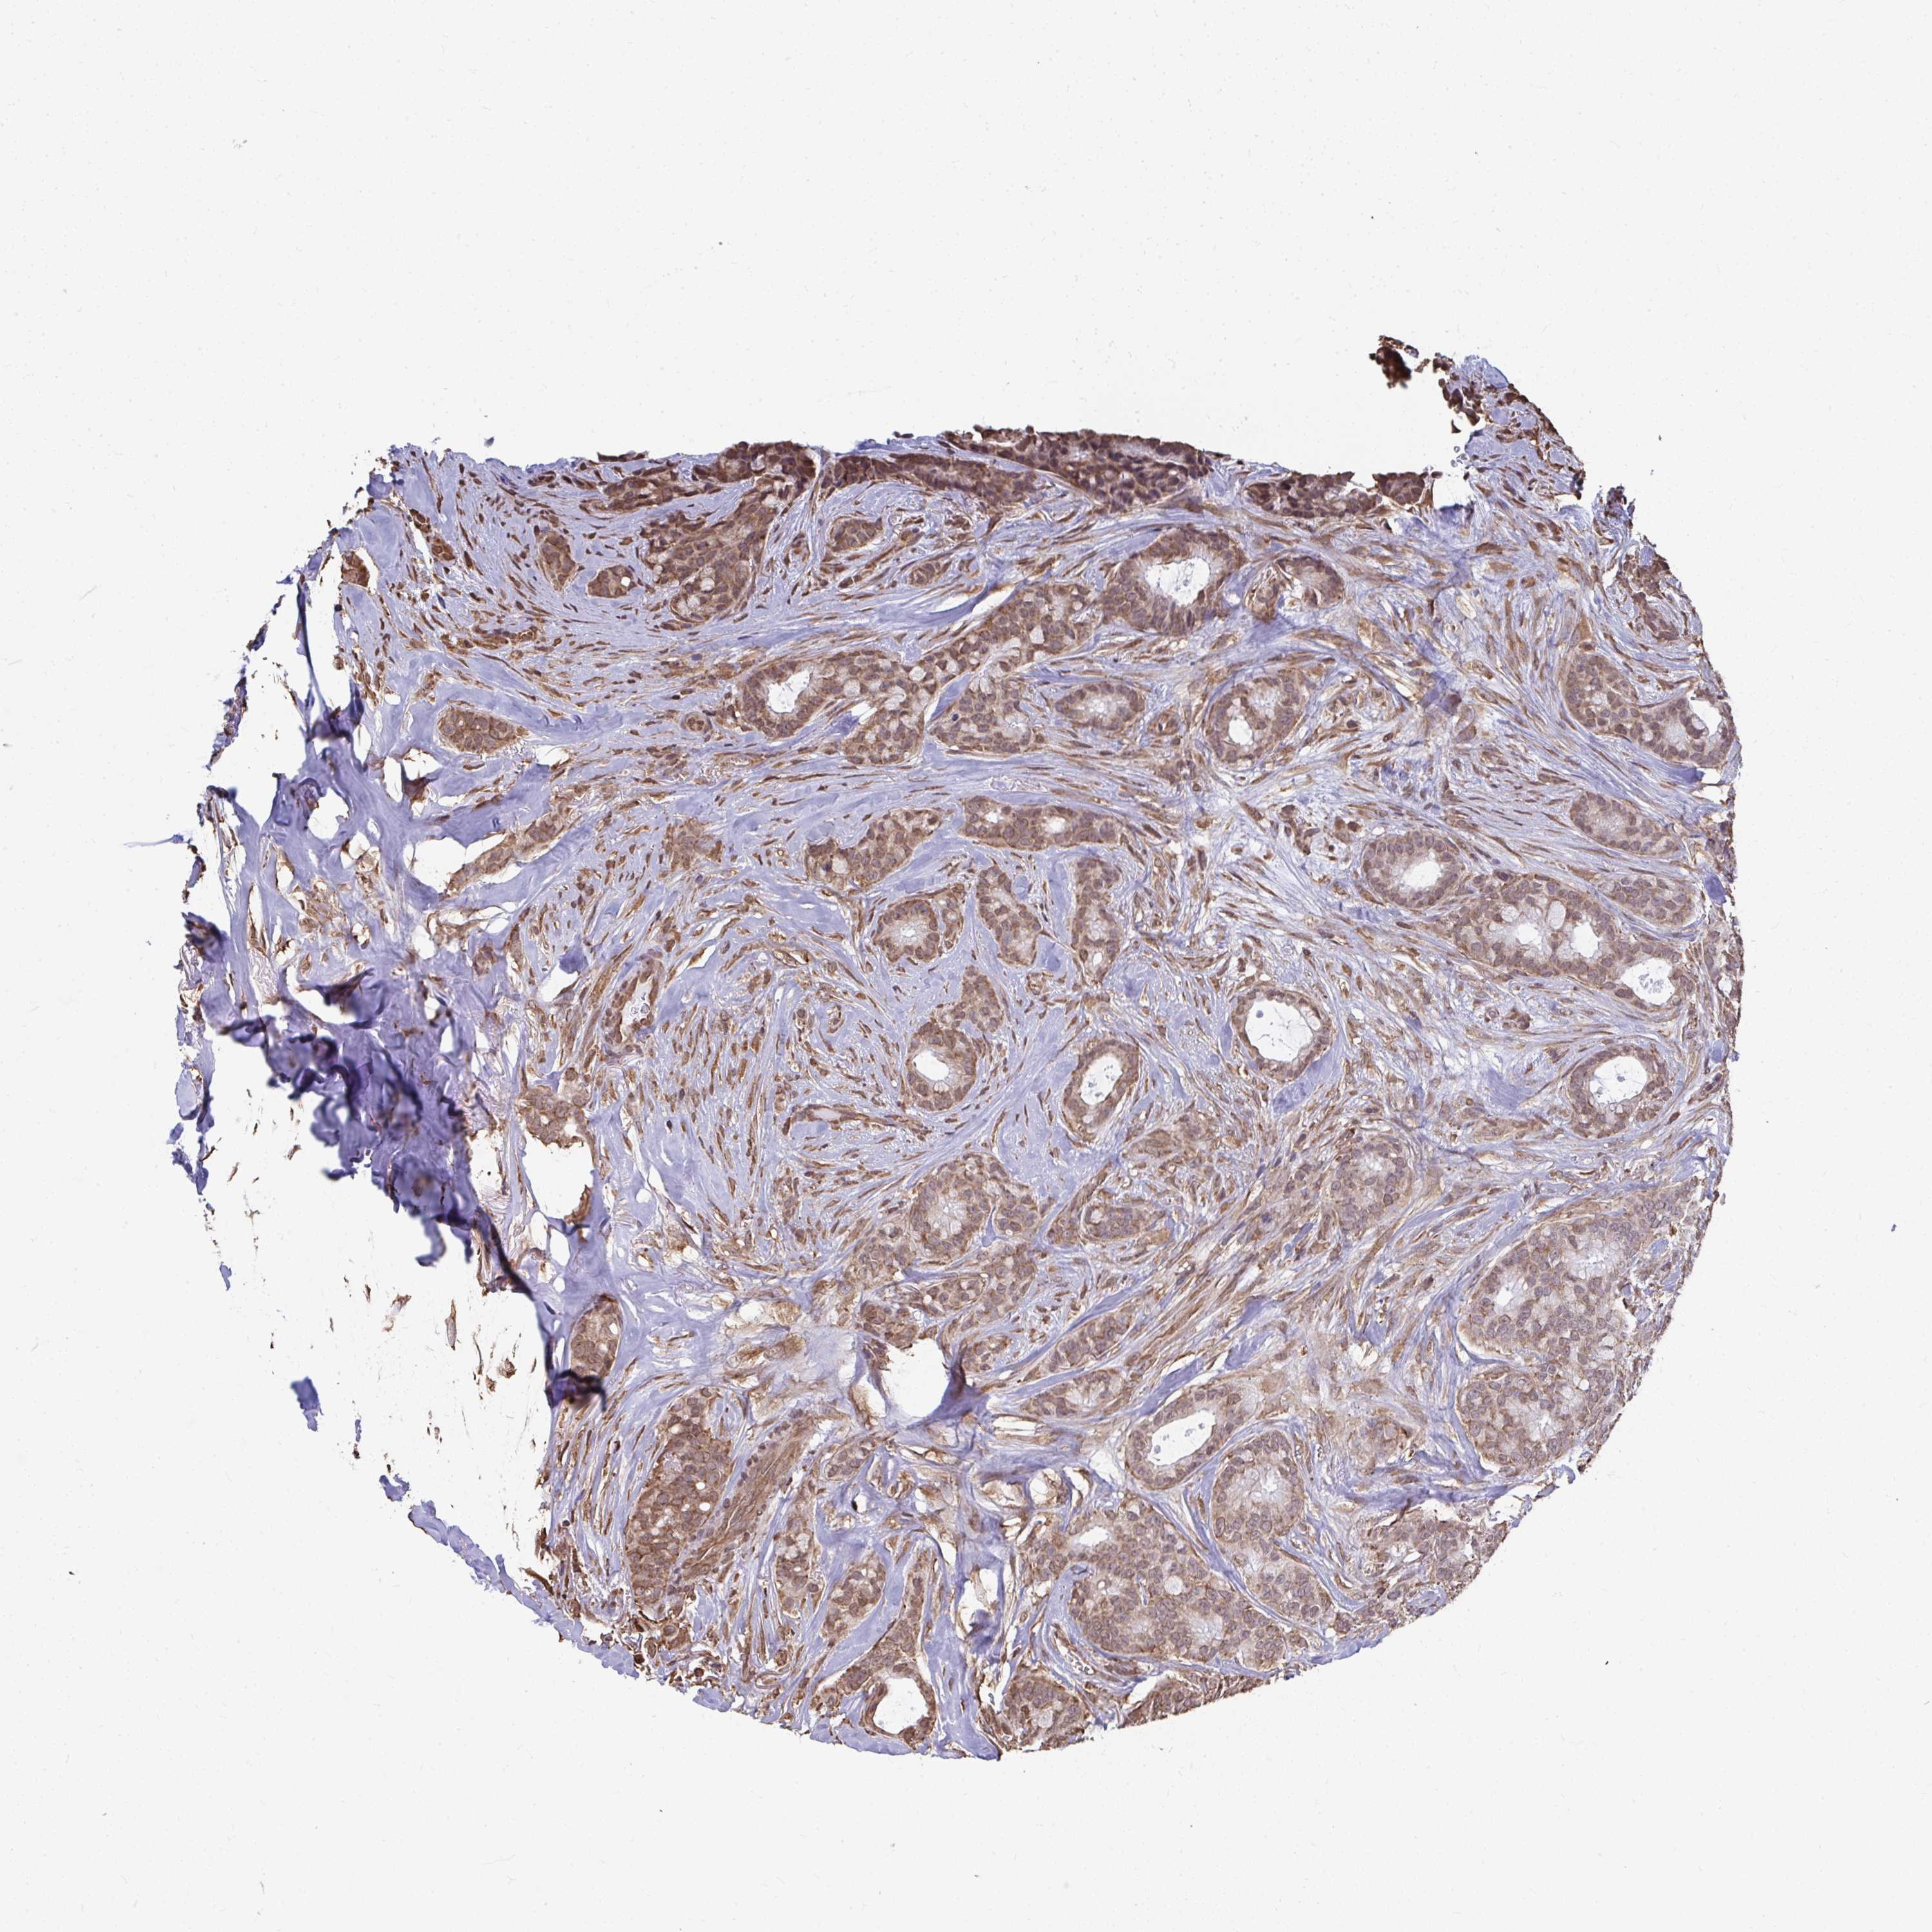

CANCER BREAST CANCER Show tissue menu

BRCA TCGA BRCA VALIDATION PROTEIN EXPRESSION

Breast cancer

Human cancer